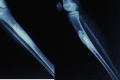

Case report: A 13 year old girl presented with pain and swelling of the (R) leg since 2 months following a trivial injury at school. Examination revealed a 5×3cm tender swelling on the anteromedial aspect of the middle third tibia. Radiographs and MRI, revealed an eccentric expansile lytic lesion, which was multilocular and was present at the junction of the metaphysis and diaphysis on the antero -medial aspect of tibia. The cortex had ballooned out and there was a possibility of an impending fracture. Biopsy was done which revealed osteofibrous dysplasia. We did an extraperiosteal excision of the lesion. To fill the cavity we harvested 10 cm of the contralateral fibula and since there was still space in the cavity, we packed bone graft substitute (hydroxyapatite crystals) into the defect. The surgical management of osteofibrous dysplasia is controversial. Various methods of treatment of such cases have been described in literature. The use of synthetic graft is an option in these patients as it reduces morbidity; and in our case we had good graft incorporation with this method.